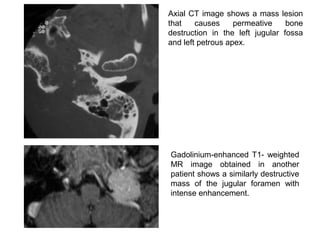

Axial CT image shows a mass lesion

that causes permeative bone

destruction in the left jugular fossa

and left petrous apex.

Gadolinium-enhanced T1- weighted

MR image obtained in another

patient shows a similarly destructive

mass of the jugular foramen with

intense enhancement.